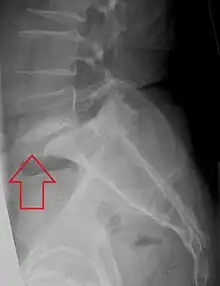

| X-ray of the lateral lumbar spine with a grade III anterolisthesis at the L5-S1 level | |

Spondylolisthesis is the displacement of one spinal vertebra compared to another. While some medical dictionaries define spondylolisthesis specifically as the forward or anterior displacement of a vertebra over the vertebra inferior to it (or the sacrum),[1][2] it is often defined in medical textbooks as displacement in any direction.[3][4] Spondylolisthesis is graded based upon the degree of slippage of one vertebral body relative to the subsequent adjacent vertebral body.[5] Spondylolisthesis is classified as one of the six major etiologies: degenerative, traumatic, dysplastic, isthmic, pathologic, or post-surgical.[6] Spondylolisthesis most commonly occurs in the lumbar spine, primarily at the L5-S1 level, with the L5 vertebral body anteriorly translating over the S1 vertebral body.[6]

Classification by degree of the slippage, as measured as percentage of the width of the vertebral body:[14] Grade I spondylolisthesis accounts for approximately 75% of all cases.[6]

- Grade III: 50–75%